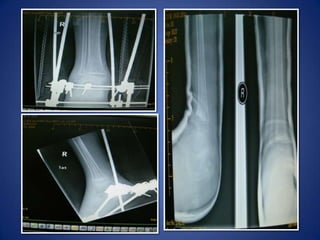

10/5/2009Post STR rt-3/M

28/10/2009

STR-dec2007(Sohar)JESS-28/10/2009KHTib AT-12/5/2010KHEXCELLENT RESULT18/4/2011